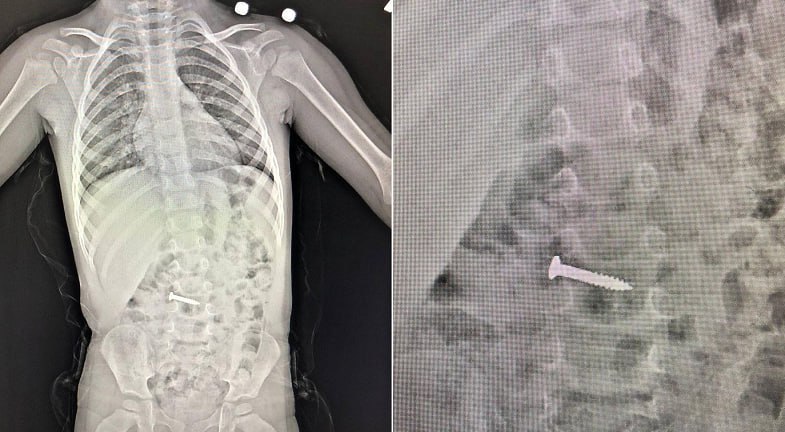

В Новороссийске 2-летняя девочка проглотила саморез, играя со старшим братом. Ребенка доставили в эндоскопическое отделение 1-й горбольницы. Операция была сложной из-за риска повреждения желудка или пищевода острым предметом.

Заведующий отделением Давид Шагинян с ювелирной точностью извлёк саморез, захватив его за шляпку специальным инструментом, чтобы избежать травм. Ребенок чувствует себя хорошо, сообщили в пресс-службе больницы.